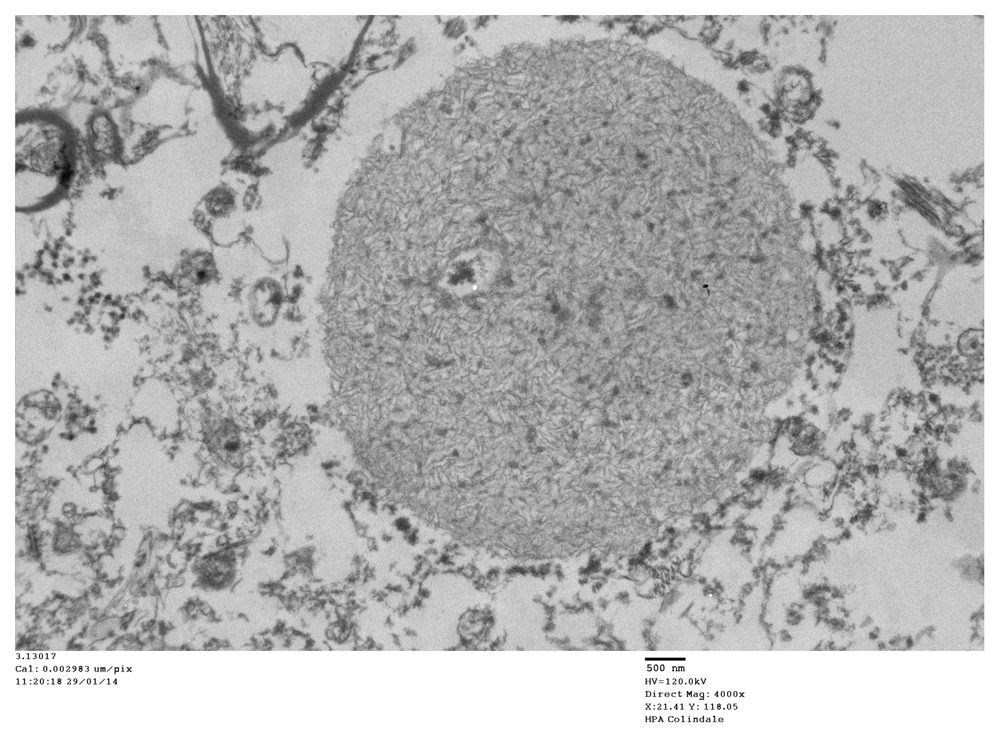

TEM changes were observed in the brainstem neurons in the PD cases and in the spinal cord motor neurons in the poliomyelitis cases. TEM of PD neurons at low magnification showed advanced apoptosis. There were almost ‘empty’ nuclei with clumped chromatin and multiple cytoplasmic virus factories. Few cytoplasmic organelles remained (Figure 1 and Figure 2). VLP were found by TEM in the nuclei and cytoplasm in the neurons of all the PD cases studied. The VLP were similar in morphology to the VLP we described in the brain of encephalitis lethargica, which had been confirmed to be a strain of enterovirus by molecular analysis1. The cytoplasmic virus factories in PD neurons consisted of large numbers of VLP interspersed with irregularly shaped endoplasmic reticulum membranes and embedded in virus factory (Figure 3 and Figure 4). VLP were observed attached to the membranes (Figure 3). The average measurements of the cytoplasmic VLP in Figure 3 and Figure 4 were both 31 nm (Table 1). Cytoplasmic virus factories in other PD neurons consisted of incomplete VLP at an early stage of assembly (Figure 5, see Discussion).

A virus factory in PD. There are endoplasmic reticulum membranes in this image (arrows). There are virus-like particles (VLP) that are larger than the ribosomes in control Nissl bodies. The mean diameter of the VLP in this image was 31 nm (see Table 1). The magnification has been adjusted to 200,000x so as to make the comparison of the diameters of VLP and that of the ribosomes more apparent. The magnification bar for 100 nm for these images = 20 mm.

In the cytoplasm of a PD case, the virus factories consisted of masses of virus-like particles (VLP) in an amorphous matrix. Mean size of VLP: 30 nm (see Table 1). The magnification has been adjusted to 200,000x so as to make the comparison of the diameters of VLP and that of the ribosomes more apparent. The magnification bar for 100 nm for these images = 20 mm.

In a previous communication, we reported the following TEM finding: the assembly in the nuclei and cytoplasm of polio virus particles and coxsackie virus particles that measured from 20 nm to 40 nm in virus factories of virus infected cell cultures1. The finding of virus particles in the nuclei of cells infected with an RNA virus was a novel observation. Virus factory has been described as a specific intracellular compartment where viral components concentrate by Novoa et al.27. Virus factories often include membrane components that are involved in virus replication. This has been demonstrated in our PD study (Figure 3 and Figure 5). The measurements we made by TEM of poliovirus in infected cells are in contrast to previous reports on the diameter of poliovirus virions using cryo-electron microscopy of purified virus preparations. In the latter studies the diameter of the virions was 30 nm. Larger diameter particles were not reported. This may be due to selection in the purification procedure of the population of virions for study28,29.

The results of TEM of PD brain are comparable to the TEM finding of virus particles found in cell cultures infected with poliovirus and coxsackie virus1. The VLP found in PD brain are also comparable to the VLP in brain from encephalitis lethargica patients1, and the virus particles found in this study in human spinal cord neurons in cases of human poliomyelitis. We had confirmed the finding of enterovirus in encephalitis lethargica brain by the demonstration of a partial enterovirus nucleotide sequence in brain tissue1. In the present study, the observation that the VLP in many of the cytoplasmic virus factories in the PD cases are larger than the cytoplasmic ribosomes from control cases was confirmed by statistical analysis (Table 1 and Table 4). In certain PD cases, the cytoplasmic factories consisted of incomplete VLP measuring approximately 20 nm. There was also a membrane component to the virus factories (Figure 3 and Figure 5). We observed that similar cytoplasmic virus factories were in the human spinal cord neurons infected with polio virus (Figure 8–Figure 10). These findings suggest that the VLP in PD represent an enterovirus infection. Intranuclear VLP, measuring approximately 40 nm, were observed in the nuclei of motor neurons in cases of poliomyelitis (Figure 11).